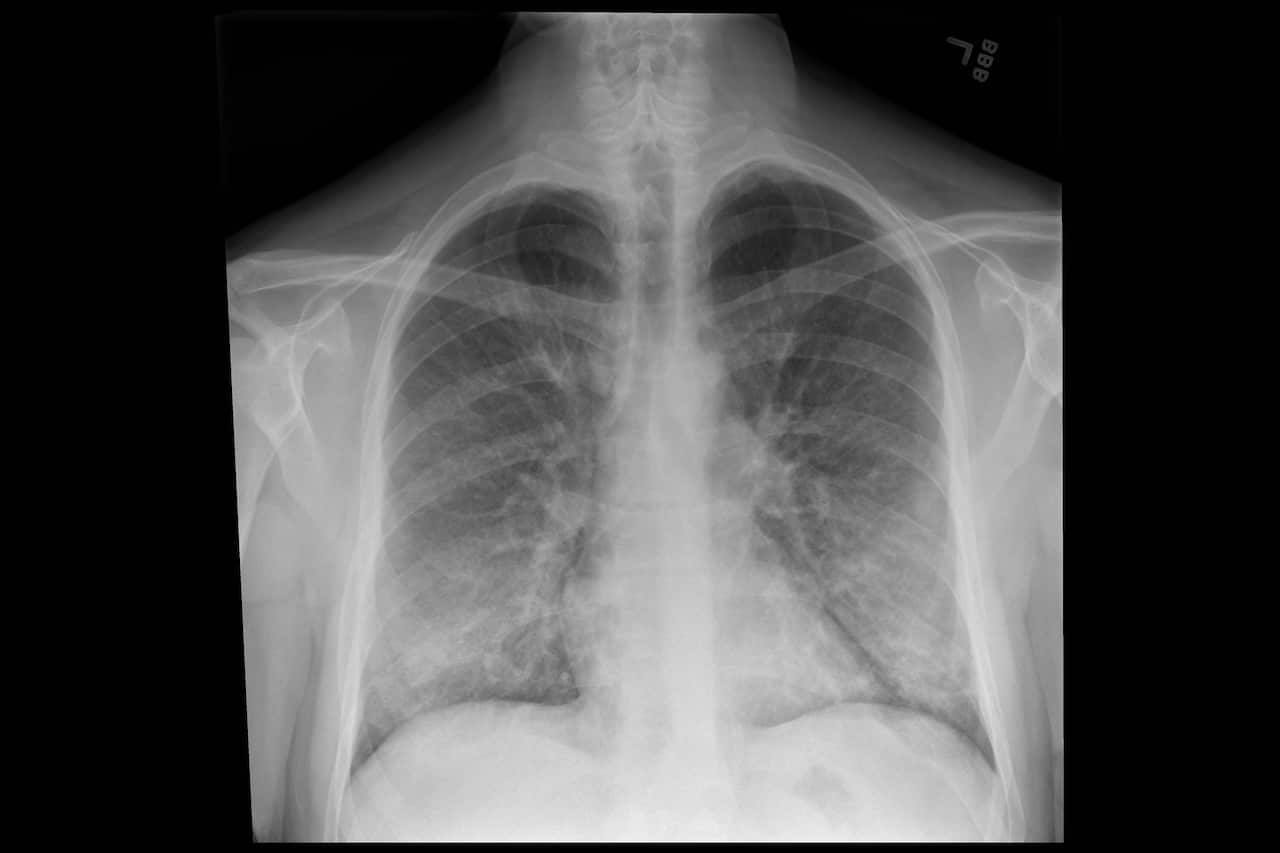

On lung scans, the illnesses look at first like a serious viral or bacterial pneumonia, but tests show no infection. “We’ve run all these tests looking for bacteria, looking for viruses and coming up negative,” said Dr. Dixie Harris, a critical care pulmonologist in Salt Lake City, who has consulted on four such patients and reviewed case files of nine others in the state.

Some patients are suffering from another condition known as lipoid pneumonia, doctors said. When vaped oils get into the lungs, the lungs treat them as a foreign object and mount an immune response, resulting in inflammation and the buildup of liquids, which can cause lipoid pneumonia.